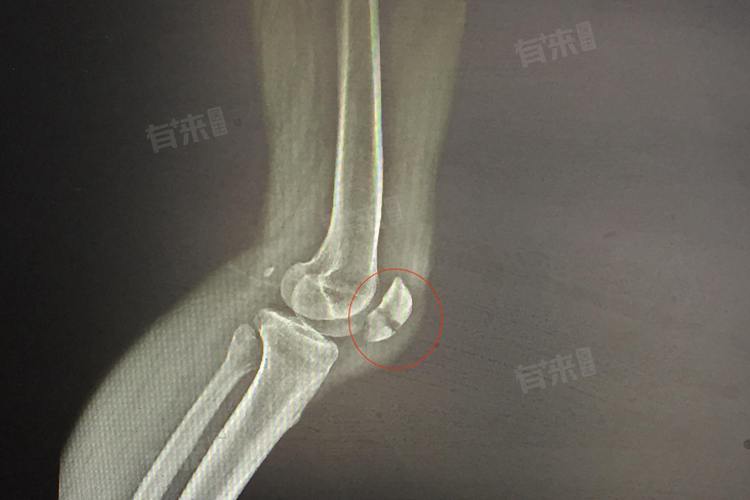

膝盖撕脱性骨折的严重程度取决于骨折部位大小、位移程度、合并损伤和患者个体情况等因素,对于膝盖撕脱性骨折,应及时就医进行准确的诊断和评估。

2、位移程度:当撕脱性骨折的骨片位移不明显时,病情相对较轻,这种情况下骨折处相对稳定,通过保守治疗如固定、休息等,有可能实现较好的愈合。但如果骨片位移明显,会破坏关节的正常结构,严重影响关节的稳定性和运动功能,此时病情较为严重。